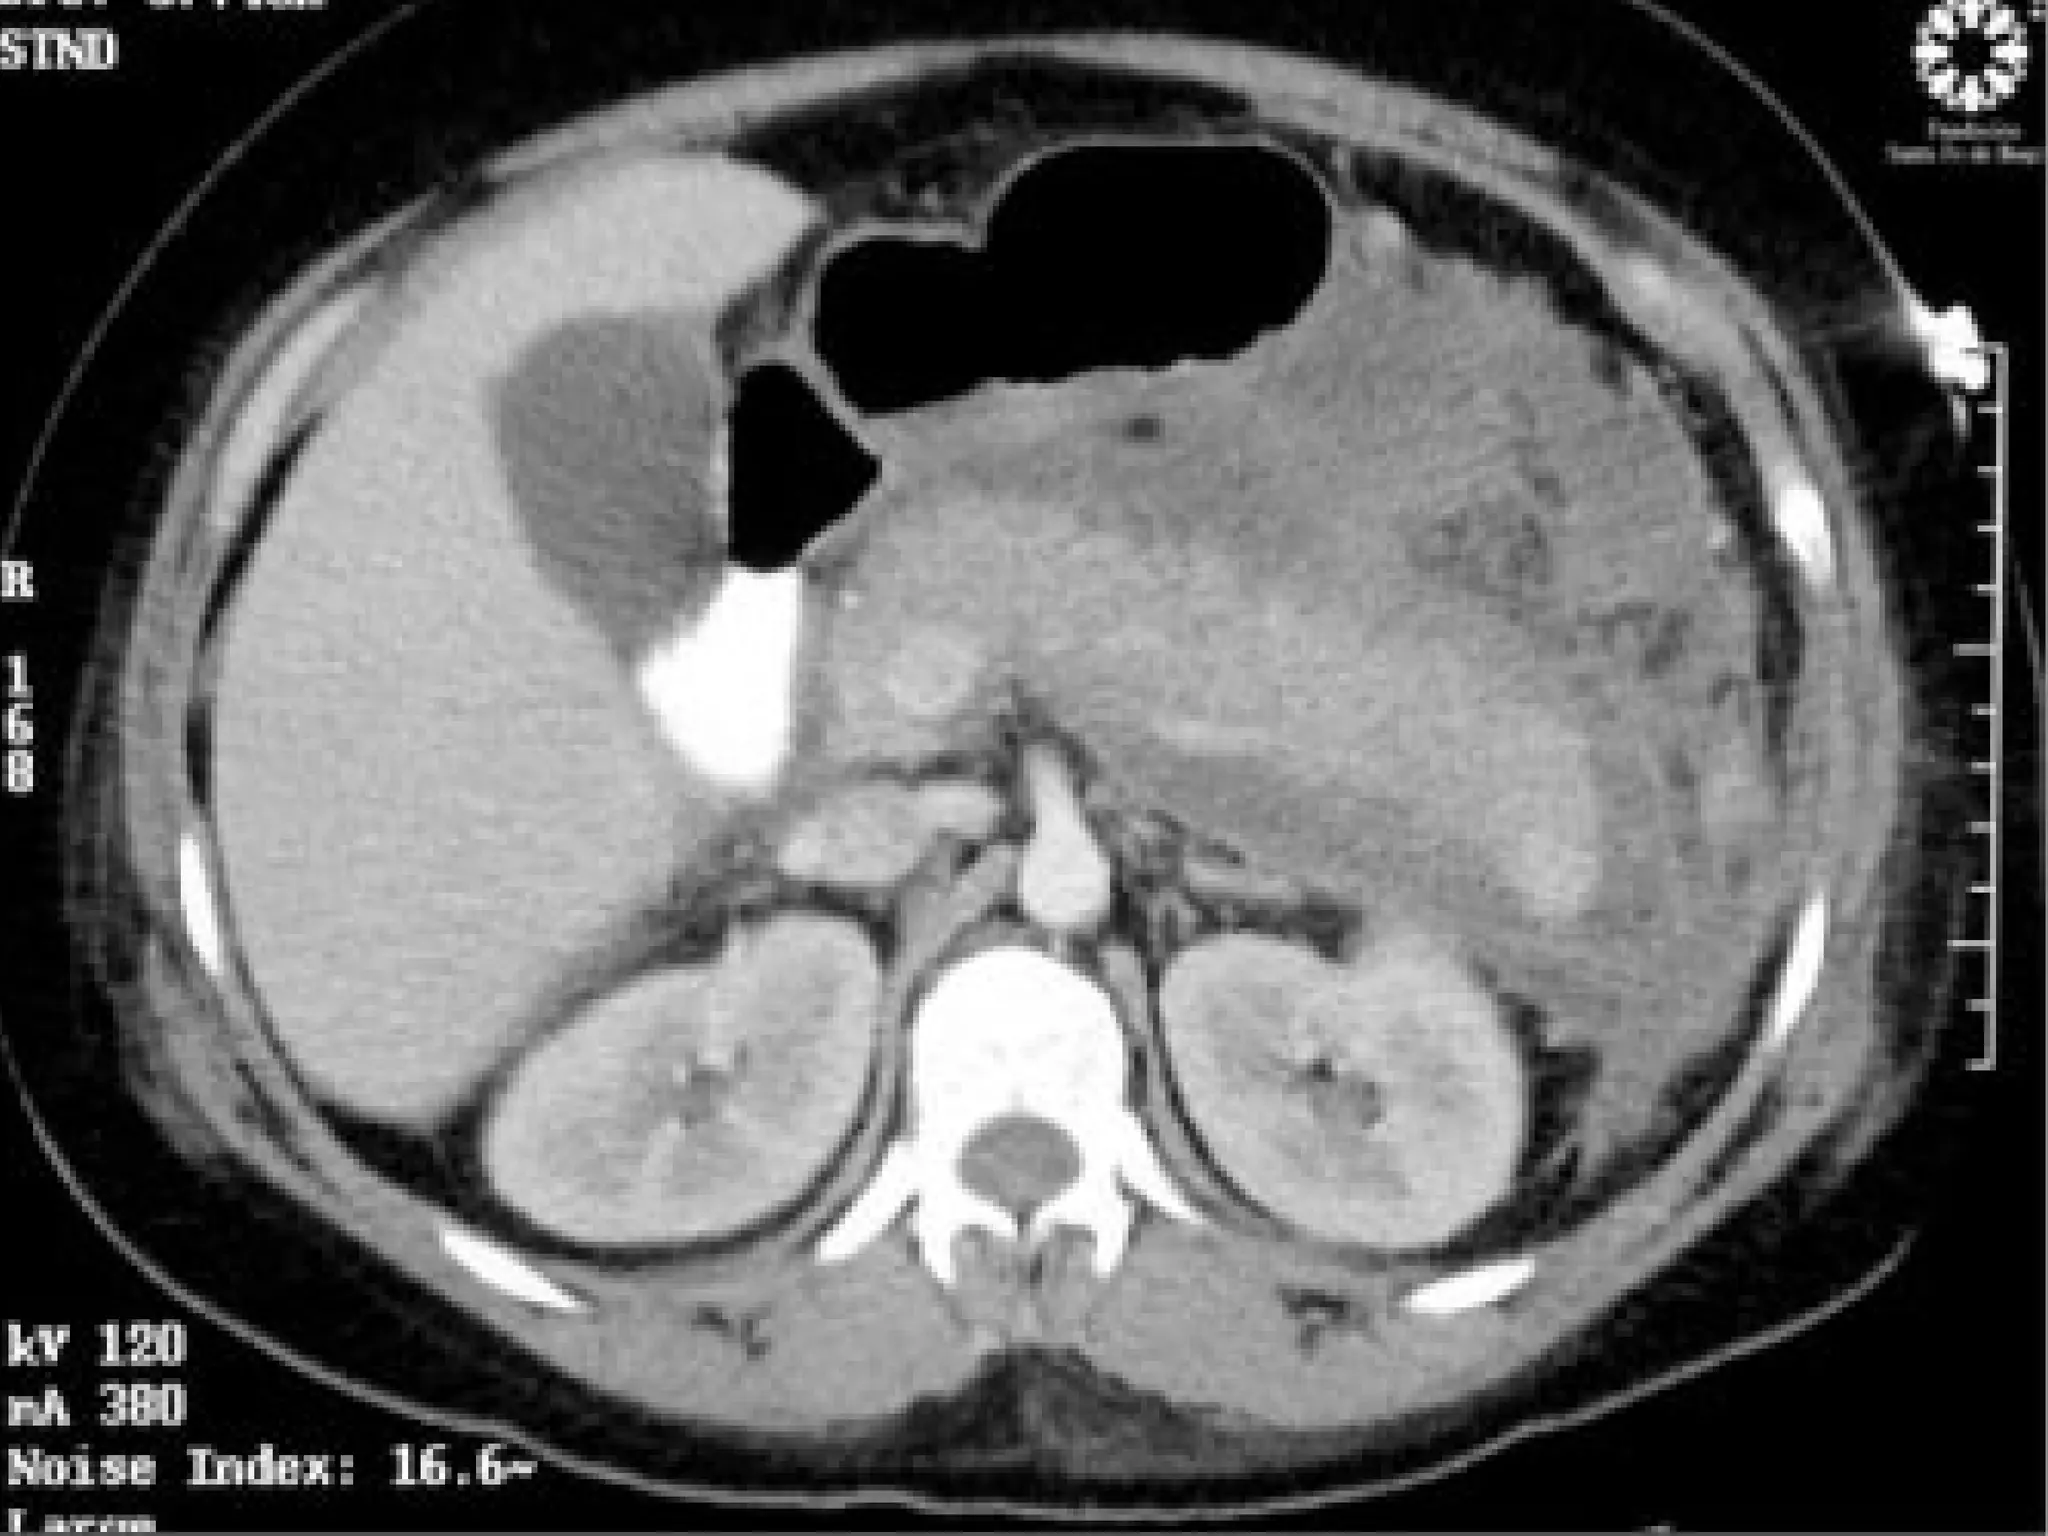

   TEM Abdominal

Exámenes complementarios:  Hemograma completo  Recuento de leucocitos  Aga y e-  EKG  Eco-abdominal  Rx torax y abdomen  TEM Abdominal  Bioquímica:  G-U-Cr  Proteínas totales y fraccionadas  Bilirrubinas TGO, TGP  Amilasa pancreática o lipasa pancreática, Fosfatasa alcalina, CPK (CPK - mb)  Examen citoquímico de orina